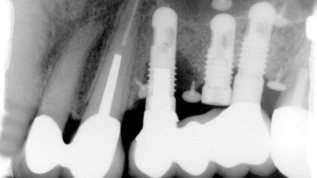

Angulierte Schraubenzugänge bei Implantat-Suprastrukturen

Jahr 2015, Ausgabe 04,

Seite 40

Autoren: Dr. Steffen Kistler, Stephan Adler, Dr. Frank Kistler, Priv.-Doz. Dr. Jörg Neugebauer